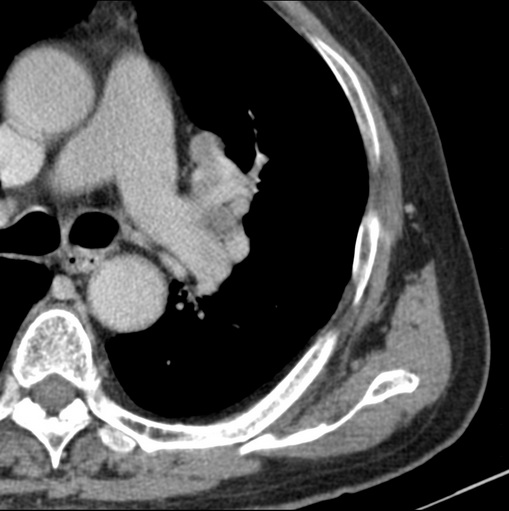

男性患者 81岁 咳嗽 咳痰 咯血

考虑左上肺癌并阻塞性肺炎,左肺转移、左肺门及纵隔淋巴结转移。

肿块贴近左肺门,包绕左上肺动脉,形态不规则。肿块增强扫描中度强化。纵膈内主动脉弓左旁间隙、气管隆突前、下间隙见多枚淋巴结影。综上考虑左侧中央型肺癌可能性大。图片没有完整上传,尤其是左肺上叶支气管分支层面没有上传,因此不好判断是叶支气管中断还是段支气管中断。另外,下图红色部分所示是“黏液支气管征”吗?